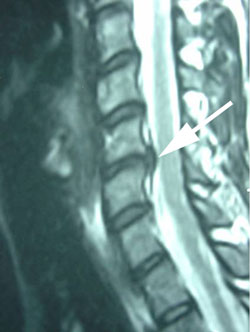

cervical instability

Figure 5 is a lateral MRI view of the spine shown on x-ray in Figures 1-4. At the arrow is the disc herniation, in this case at the C5-C6 level, where we see the instability and backward movement of the C5 vertebra on C6 below it. This disc herniation is also shown in Figure 6 below in an axial or cross cut view through the disc space at C5-C6 showing the disc herniation compressing the nerve to cause the arm pain that this patient complains of.  (See the large arrow.)

active inflammation in the cervical spine disc

Note in Figure 6, at the small arrow, the white dense material within the disc herniation; this signifies active inflammation within the disc and such inflammation is considered a source of pain. Also note that this disc herniation also contacts the spinal cord as shown at the yellow arrow.